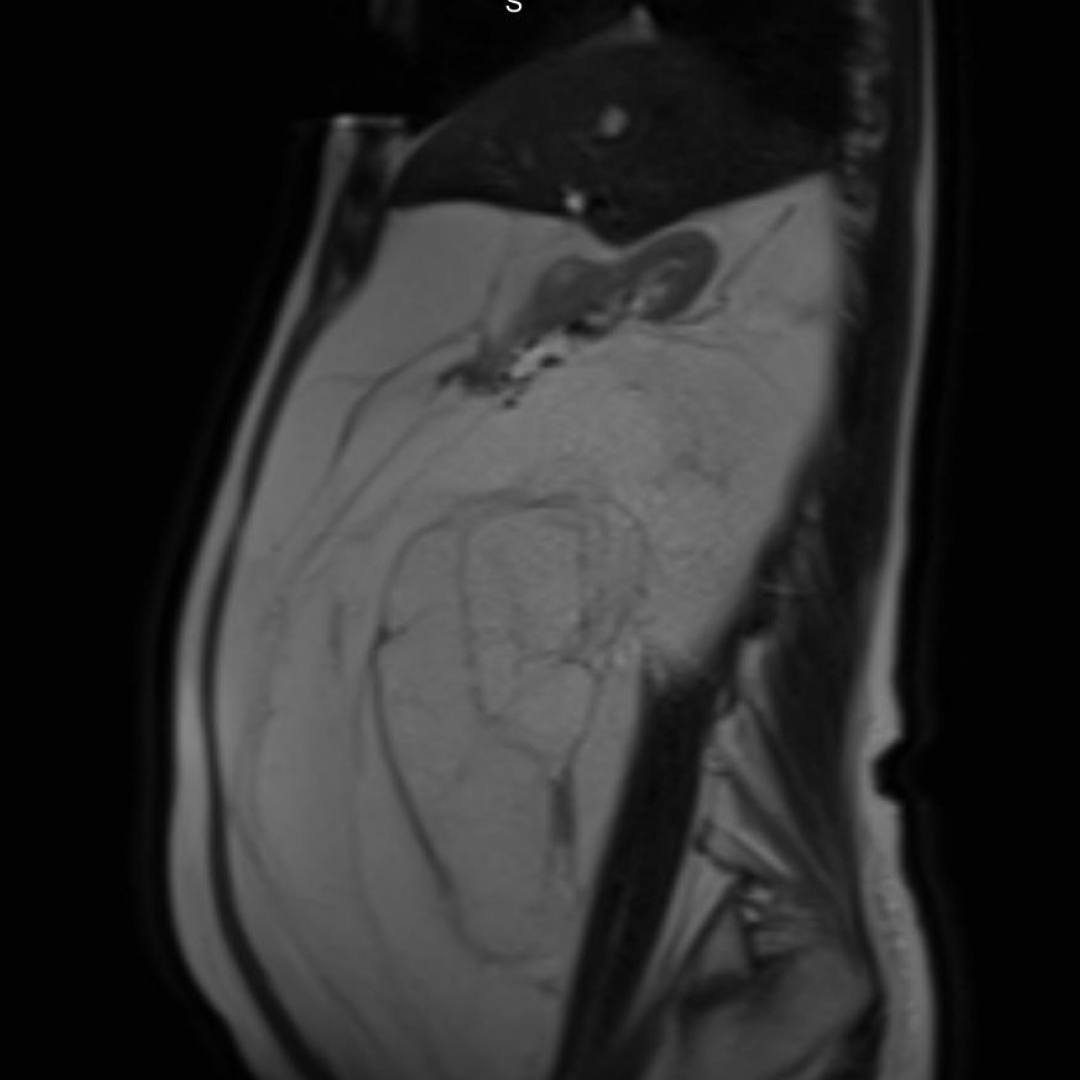

С целью оценки образования, а также уточнения расположения и взаимоотношения с органами брюшной полости проведено МРТ органов брюшной полости с внутривенным контрастированием.

При МРТ было выявлено жиросодержащее внеорганное объемное образование больших размеров с множественными неравномерными накапливающими контрастный препарат перегородками, занимающее большую часть брюшной полости с признаками смещения прилежащих внутренних органов.

Учитывая особенности структуры образования, распространенность и расположение, находка расценена как липосаркома (злокачественная опухоль жировой ткани).